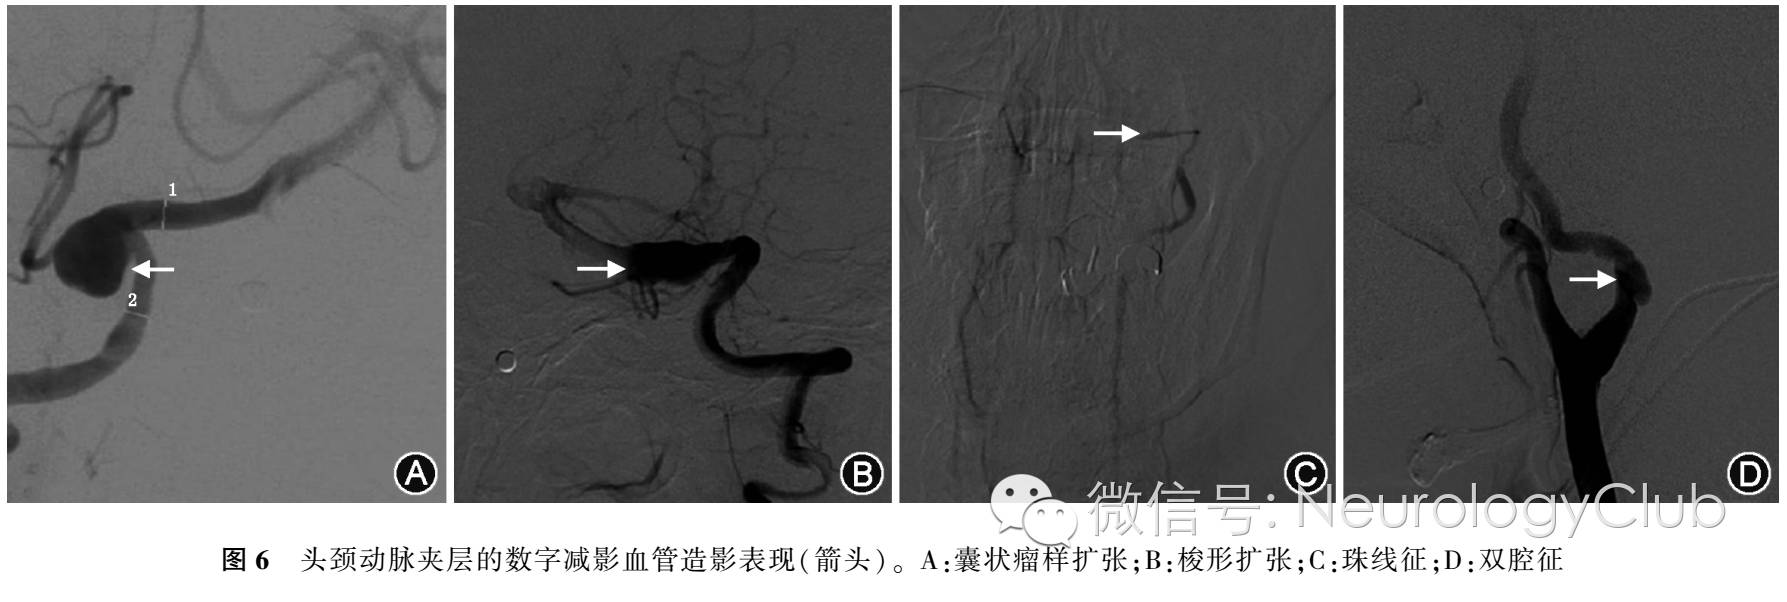

(三)DSA对动脉夹层的诊断

DSA一直被认为是诊断和随访动脉夹层的“金标准”。然而,这种技术有时也不能给出动脉夹层的确切诊断,因为它不能显影动脉壁和管壁内血肿的形态。DSA是诊断颈动脉夹层的可靠手段(图6)。影像学所显示的夹层部位和形态特征与患者的临床表现的关系具有一定的规律。DSA有其局限性,即动脉壁的厚度及外形不可见。最常见的是线样征,指从颈动脉窦远处长而逐渐变细的狭窄,通常为偏心且不规则,还有珍珠征(指管腔)、局灶性狭窄、远端扩张为夹层动脉瘤、火焰征(指管腔逐渐变细至闭塞)、夹层动脉瘤、管腔内血栓形成、血管串珠样狭窄(通常提示存在纤维及营养不良或其他血管病)。